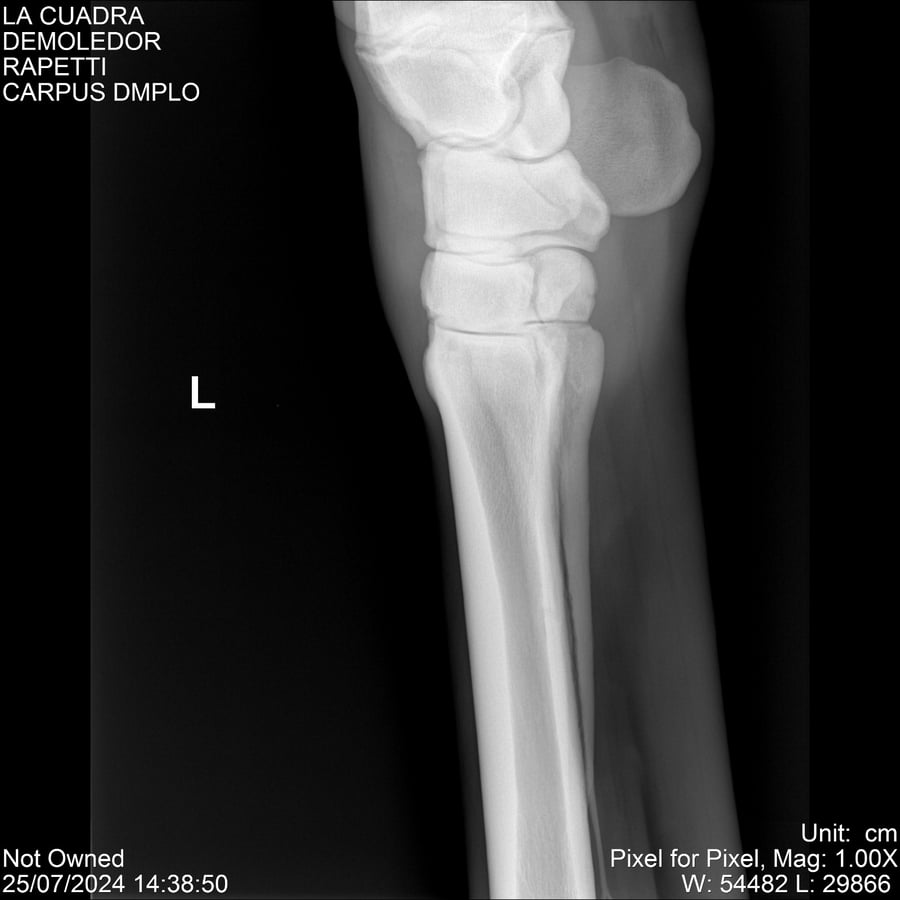

LOTE 14, DEMOLEDOR 🔥 🔥 🔥 Lote Anterior Volver al remate Lote Siguiente Ficha Contacto Montevideo - Ficha del Lote Identificador: #284454 Categoría: Yeguarizos Montevideo - 89 Visualizaciones ClicData Contacto Empresa: Abelenda N. R., Walter Hugo Nombre*: Teléfono* : E-mail* : Mensaje Enviar Registrese gratis Este contenido Exclusivo está disponible sólo para usuarios registrados Ingresar